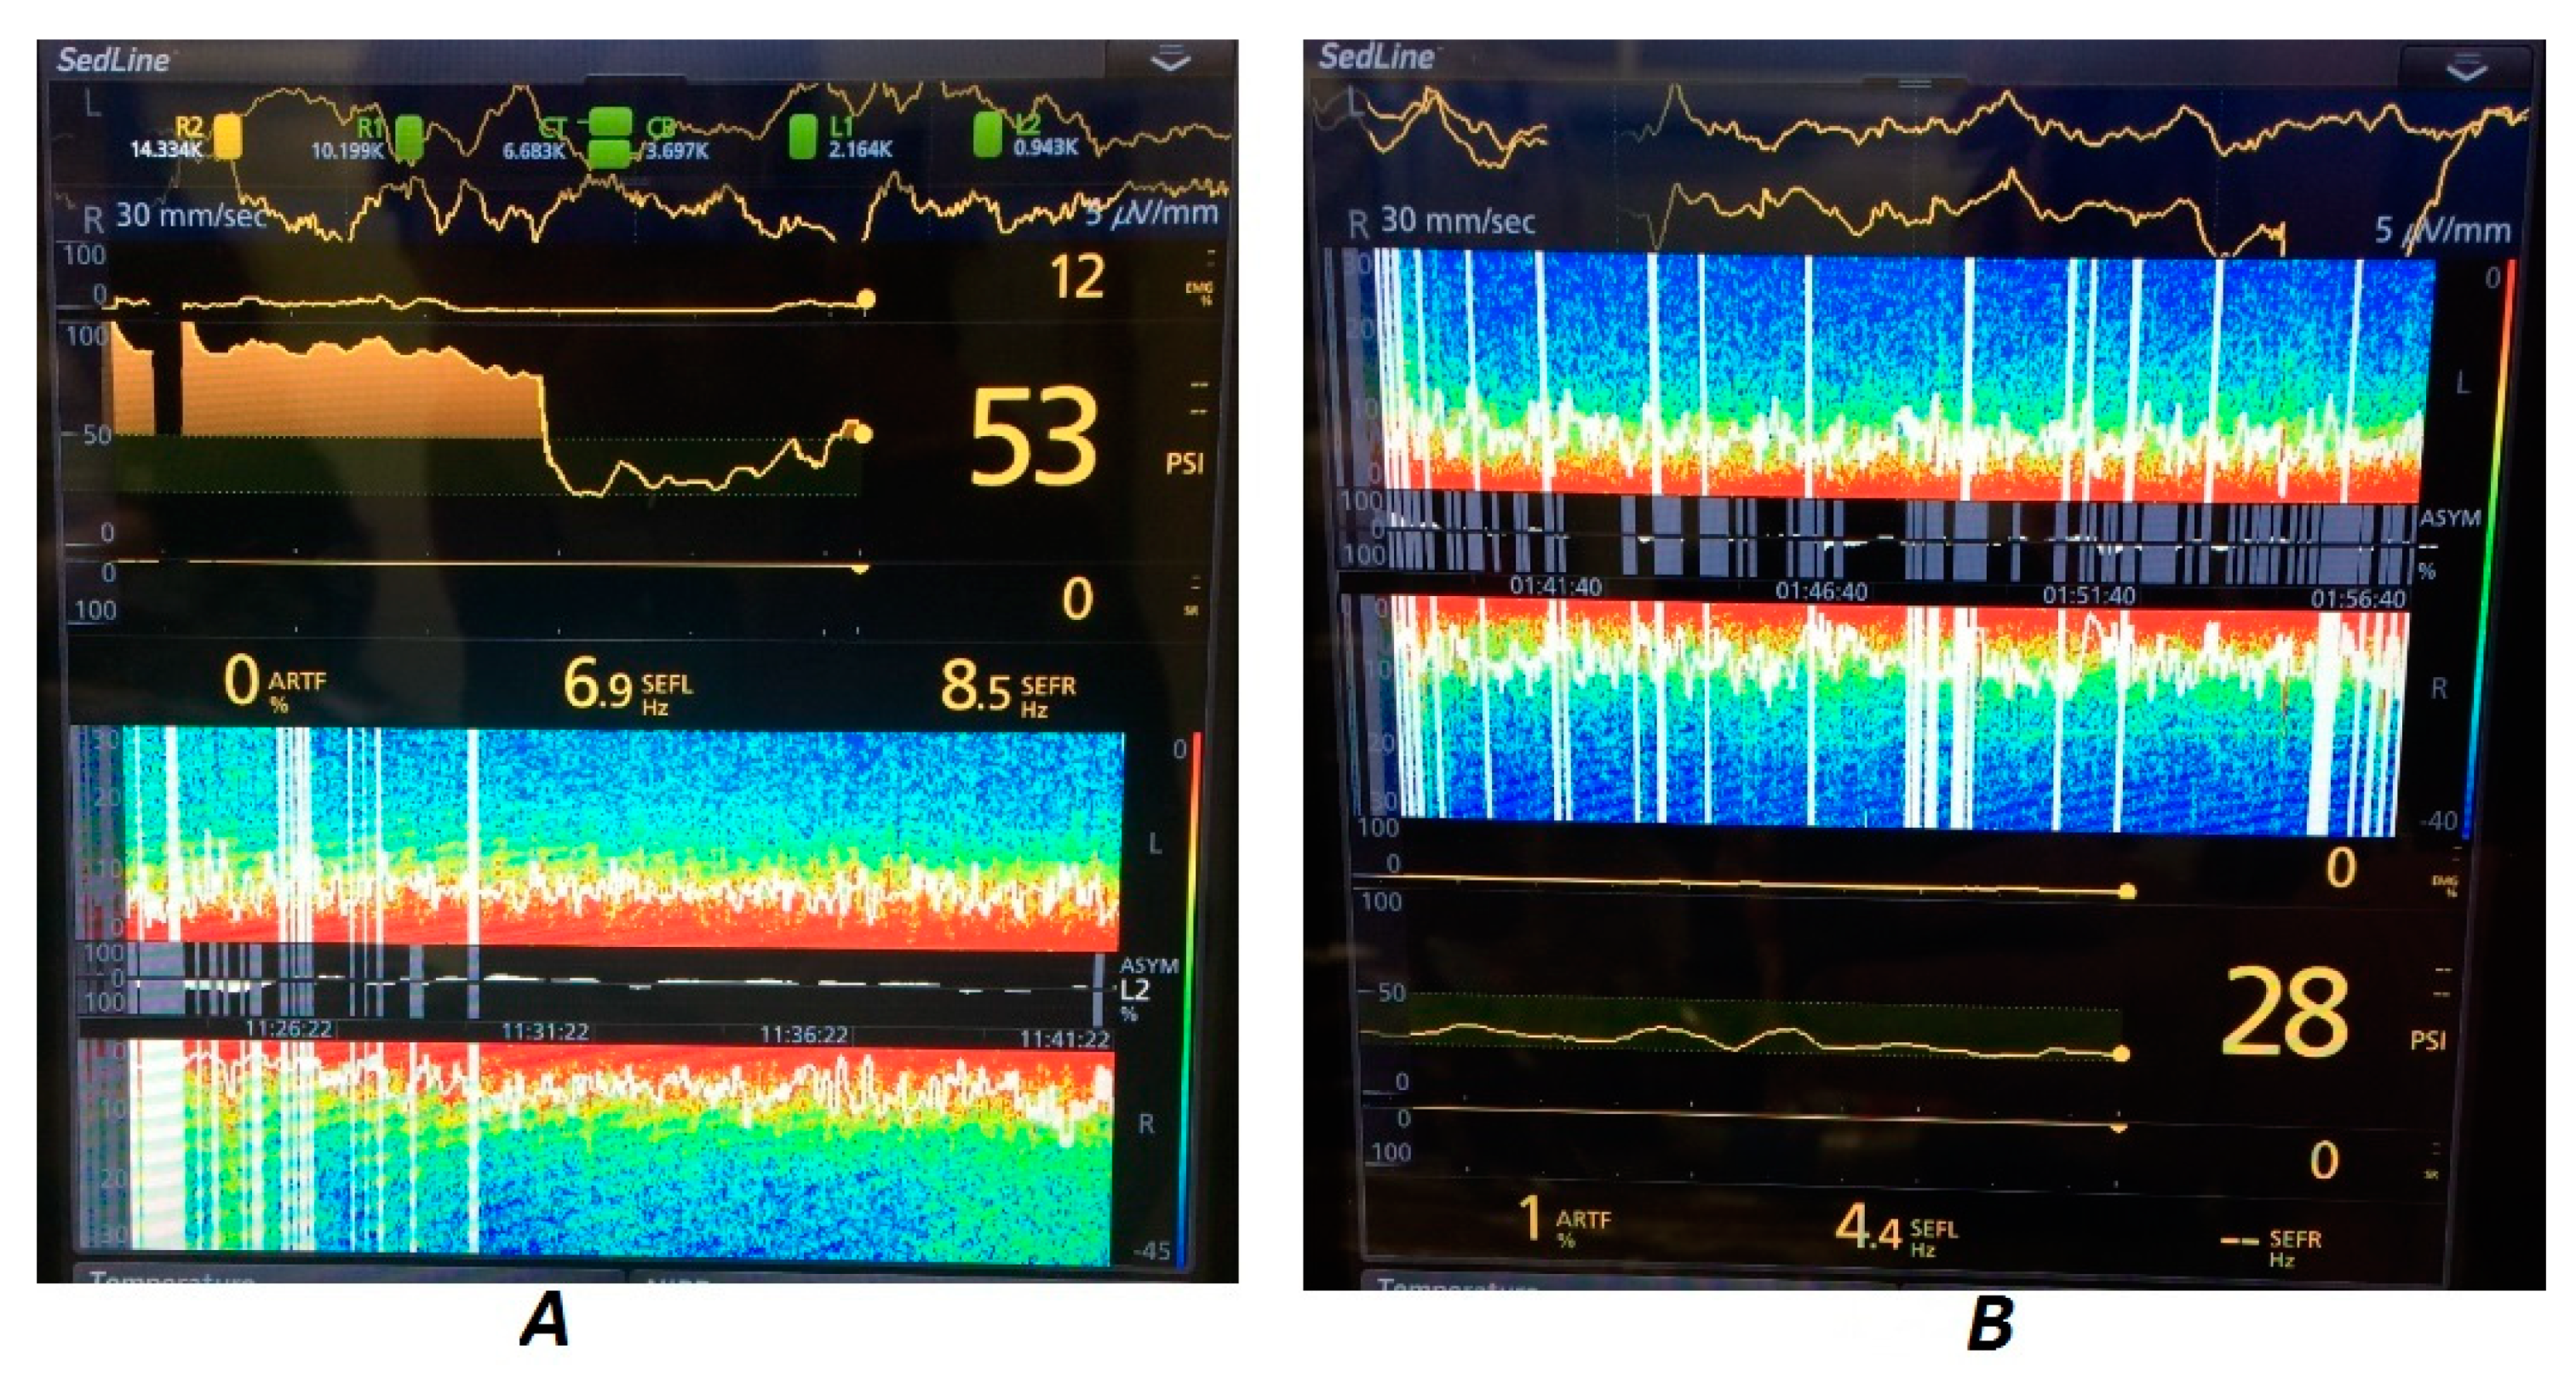

During colic surgery (Horse B), which lasted 3 h, there was extensive variability in the frequency and power of the EEG waves recorded. The horse was in a critical clinical condition before the surgery and its hemodynamic parameters changed significantly during the maintenance of anesthesia. The DSA was recorded without artifacts. In-tidal isoflurane concentrations and supplemental medications were adjusted as needed to maintain cardiopulmonary function and assure desirable pain management. Significant jumps in the SEF and power of higher-frequency waves could be seen during more painful moments—skin cut, enterotomy, and skin suturing at the end. Also, periods of high power of high-frequency waves could be seen (Figure 5).

In the case of castration (Horse C), the SEF was also variable but the waves of significant (for overall arousal) power were present only within short frequencies. There were no periods of higher-frequency waves emerging during the whole procedure. The hemodynamic parameters were stable. The horse was kept in a light plane of anesthesia. There were sporadic artifacts visible. During the whole procedure, the appearing waves were stable in power within their frequency bands (Figure 5).

Figure 5. EEG DSA during colic surgery (Horse B) (A) and castration (Horse C) (B). Note the differences between the power levels in various frequency bands during colic surgery, which indicates changing levels of awareness as well as possible pain sensation, while during castration the highest power was focused on low-frequency waves, which indicated a low level of awareness. Even though the SEF was not stable during castration, the waves of higher frequency occurred sporadically and had such a low power that they did not influence the overall anesthetic depth.